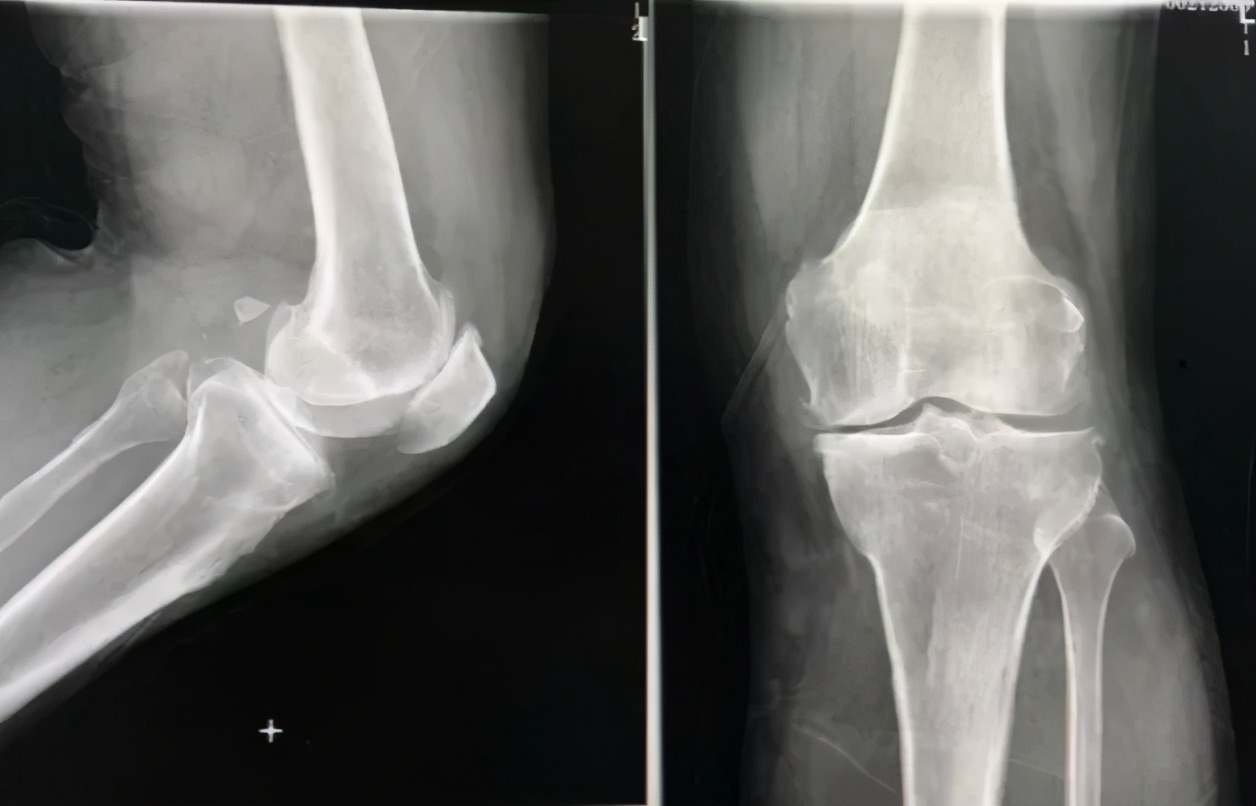

患者郑先生,58岁,双膝关节反复肿痛十余年,去当地医院检查,诊断高尿酸血症,间断性口服降尿酸药物,未规律复查。近一段时期,疼痛加重,尤其左膝关节内侧疼痛厉害,并内翻畸形,走路困难。

为求进一步诊治,一周前慕名来到上海市第六人民医院临港院区关节外科刘万军主任处就诊。根据以往的病历资料显示,郑先生是由于尿酸控制不佳而导致的痛风反复发作,最终导致膝关节结构性破坏。

据刘万军主任介绍,痛风性膝关节炎是指患者因体内嘌呤代谢紊乱,使得尿酸盐结晶体在关节组织中沉积,进而诱发炎性反应的一种疾病。痛风性膝关节炎可反复发作,极易破坏关节骨质,诱发关节疼痛及活动受限等症状,严重影响患者生活质量。

(术前)